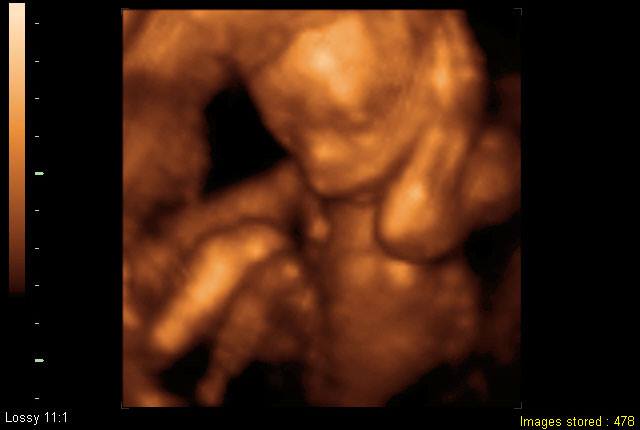

Ultrasound sound

Ultrasound sound Introduction Ultrasound sound waves that have a higher frequency than the human ear can hear the sound waves that are used in photography,There are frequencies ranging from 20 KiloHertz (KHz / acoustic) or more.Which this sound wave is used in medicine, both in diagnosis and in the treatment of specific diseases mentioned in the diagnosis of doctors who use ultrasound for disease examination.With the various ultrasound machines, the benefits of ultrasound, and each device has a different price.

Body 1 There are 2 types of ultrasound.2D ultrasound machine Will get the image in the 2-dimensional plane, ie wide and long, like a long cut image Or blocking objects When using this type of ultrasound, see the fetus.3D ultrasound (3D) or 4-dimensional ultrasound (4D)Ultrasound will be a scan. Looking like sweeping the surface of the outer surface, like we watch the person, is a 3-dimensional image that is wide, long and deep, but will not see the internal organs of that person, Like a movie that looks easy Very useful To diagnose abnormalities of external organs such as cleft lip, fingers or toes, etc.

Boby 2 There are many benefits of ultrasound. Whether it is using pregnancy tests Used to diagnose diseases Used for detecting, detecting or detecting abnormalities in general, using suspected organs for diagnosis and treatment and use in medical procedures. Therefore, the ultrasound device has different benefits depending on each type.

Body 3 The price of the ultrasound machine will vary depending on the size or use of the treatment. For example, using ultrasound to check for pregnancy will have an estimated treatment fee at each time 1500-2000 baht.Or using 3D or 4-dimensional ultrasound machines The price will be around 2500-4000 baht, etc.

Conclusion Ultrasound equipment is a scientifically important medical device.Both in the treatment of diseases or pregnancy tests Check channel And finding various diseases.By which the ultrasound device will have different price or usage charges depending on the public and private hospitals.